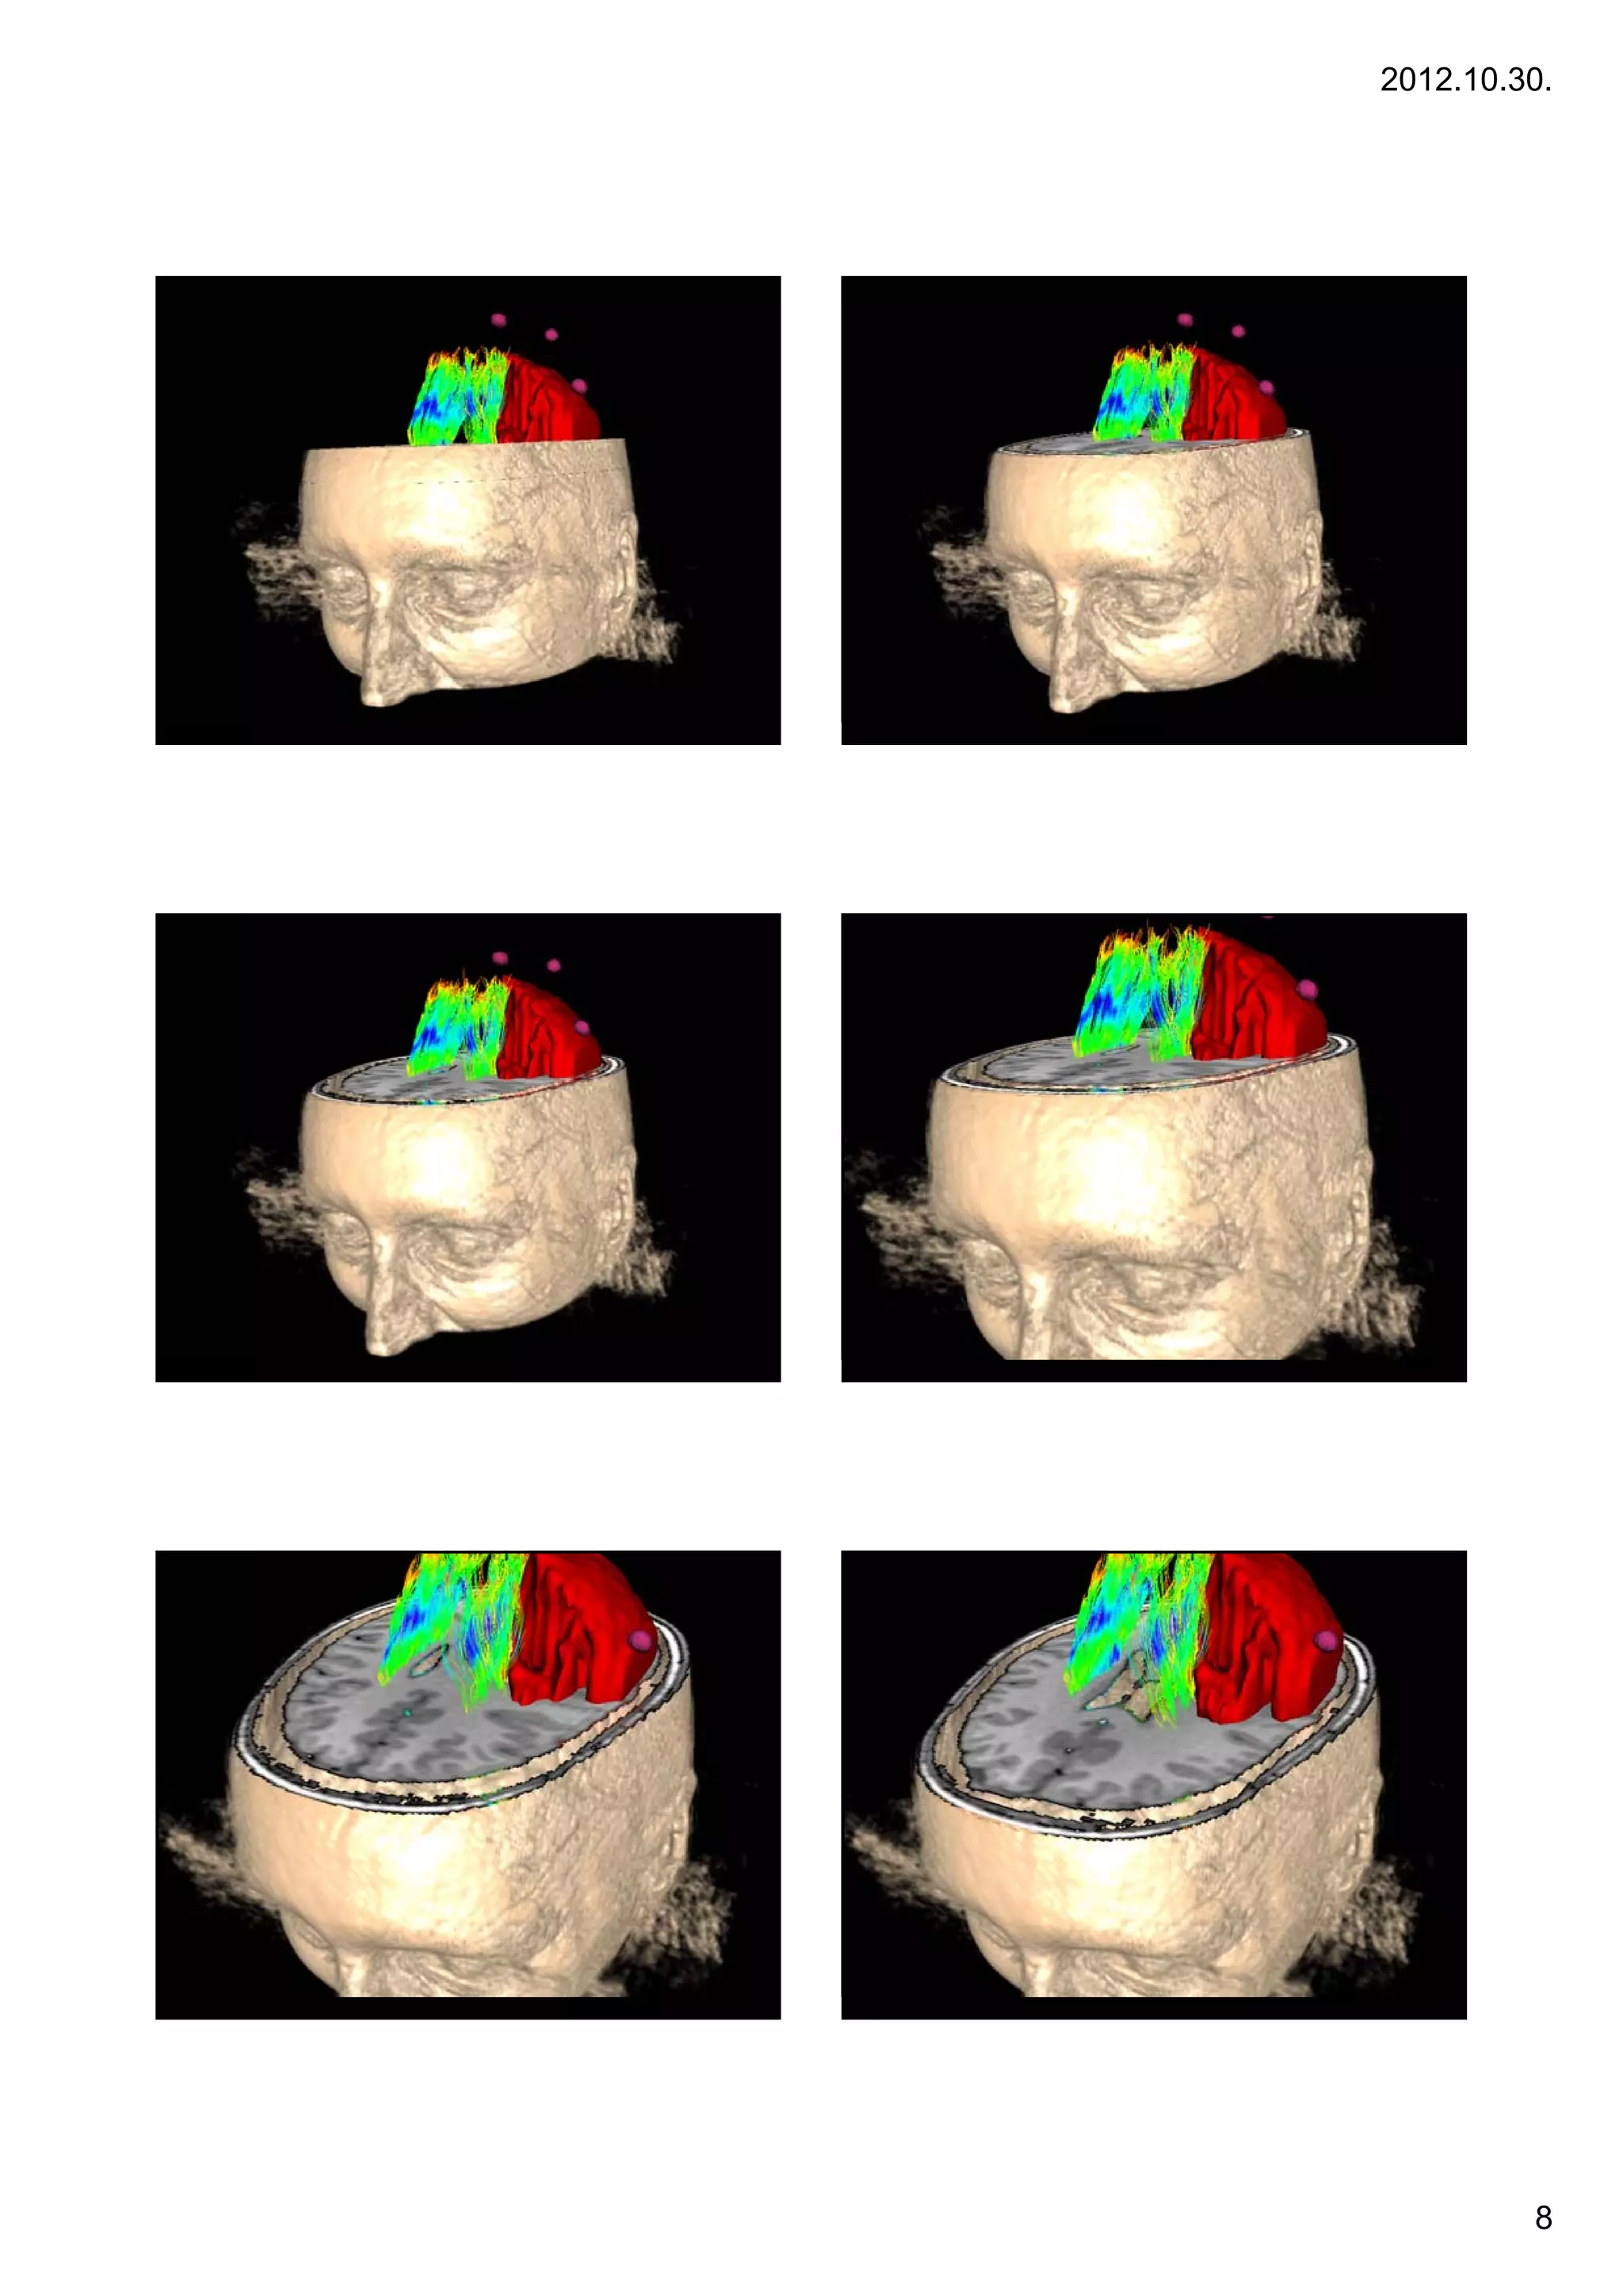

Bevezetés                                Bevezetés

43   A multimodális képalkotás alapjai   44   A multimodális képalkotás alapjai

45   A multimodális képalkotás alapjai   46   A multimodális képalkotás alapjai

47   A multimodális képalkotás alapjai   48   A multimodális képalkotás alapjai